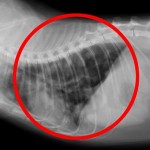

개의 항문주위선종

항문 근처에 발생하는 종양입니다. 중성화 수술(거세)로 발생율을 낮출 수 있기 때문에 남성호르몬과 연관성이 크다고 생각됩니다. 수컷에게서만 발생하며, 암컷은 매우 드문 편입니다.

악성의 경우에는 항문주위선암으로 불리우며, 이 경우에는 치료가 어렵습니다. 구별하기가 어려우므로 서둘러 검사를 받는 편이 좋습니다.